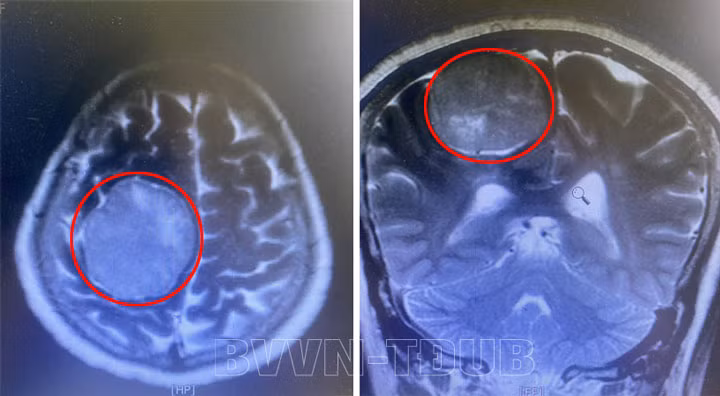

Ca mổ kéo dài gần 3 tiếng, các bác sĩ lấy được toàn bộ khối u mà không làm tổn thương đến các cấu trúc khác của não.

![]() |

| Phim chụp lại sau phẫu thuật |

Sau 10 ngày theo dõi và điều trị, người bệnh tỉnh táo, sức khỏe ổn định và đã được xuất viện.